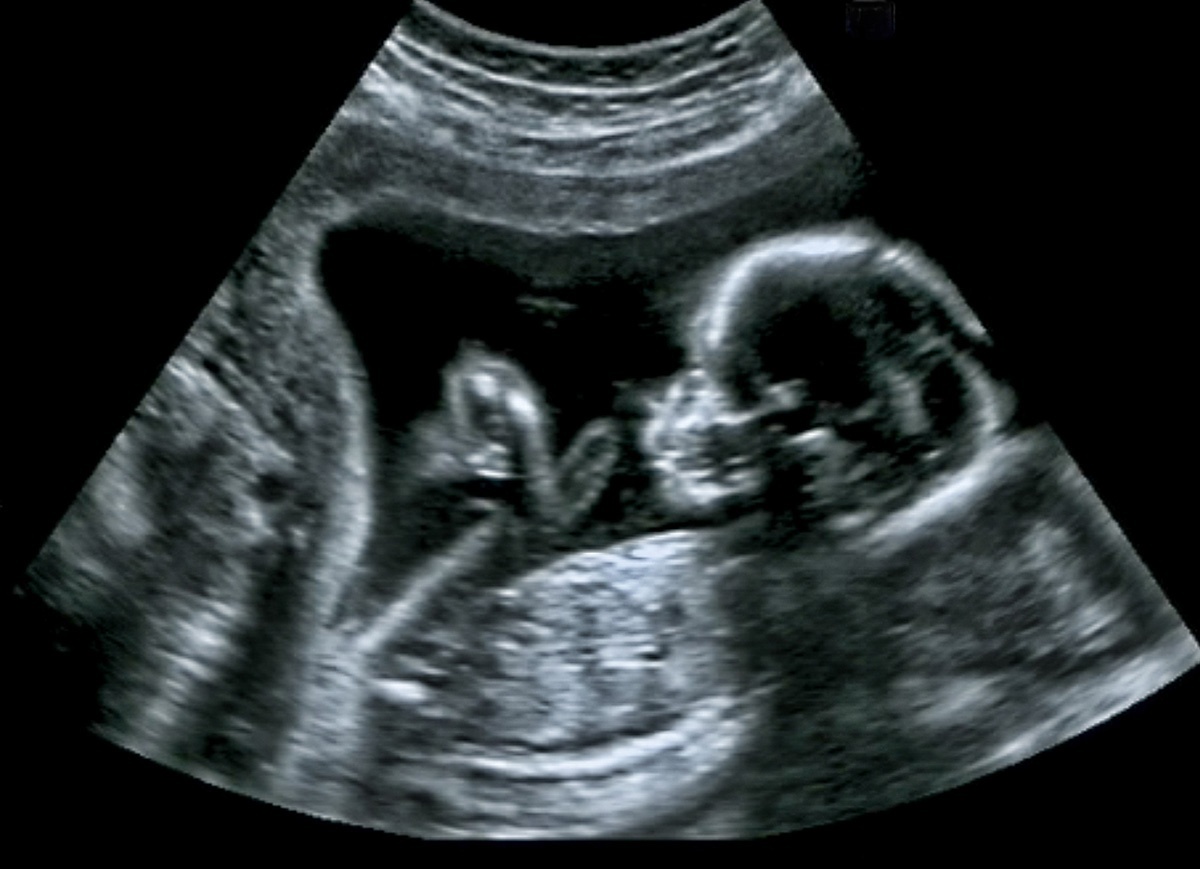

Kids of any age can be introduced to the beauty of fetal development using picture books and online resources. Haul out the video or photo of their ultrasound, if you have one. Every Catholic child should know the basics about human development: human life begins at the moment of conception, when the individual begins to grow according to the plan mapped out in his or her unique DNA; the human heart begins beating at about 18 days; the fetus begins responding to touch (and pain) between 6-8 weeks; babies are viable beginning at about 24 weeks.